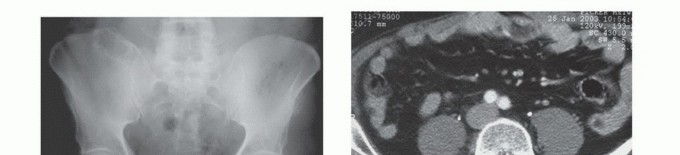

- الأشعة السينية (X-rays): هي الفحص الأولي، ويمكن أن تكشف عن التغيرات العظمية مثل التآكل أو التصلب أو الكسور.

- التصوير المقطعي المحوسب (CT Scan): يوفر صورًا مقطعية مفصلة للعظام والأنسجة الرخوة، ويساعد في تحديد حجم الورم، مدى انتشاره داخل العظم، وعلاقته بالهياكل المحيطة.

- التصوير بالرنين المغناطيسي (MRI): يُعد الأداة الأكثر حساسية لتقييم الأنسجة الرخوة ونخاع العظم، ويكشف عن النقائل في مراحلها المبكرة، ويحدد مدى انتشار الورم في القناة الشوكية أو الأعصاب.